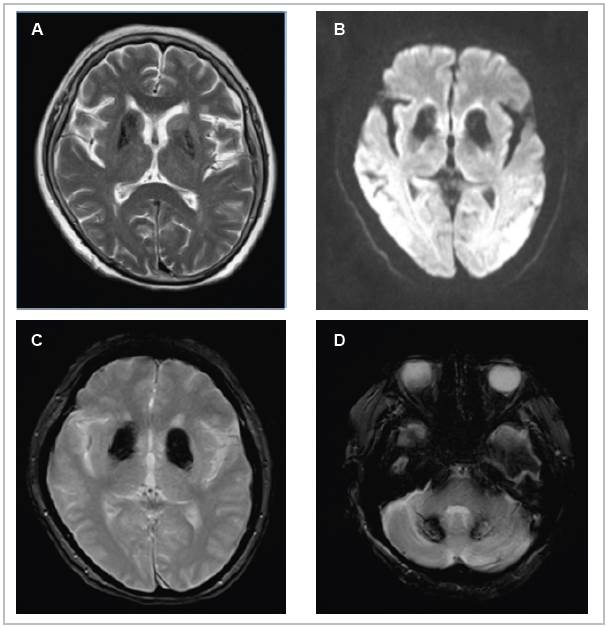

Considering the lateralization of the symptoms and the sudden onset of the condition, magnetic resonance imaging was ordered to rule out an ischemic cause, with the following findings: changes in signal intensity in the basal ganglia and both cerebellar lobes, related to mineral and/or calcium deposit disease; chronic microangiopathic changes; moderate cortical atrophy; and peripheral thickening of the left maxillary sinus mucosa. These results were corroborated with the previously mentioned simple head CT results, thus determining a diagnosis of Fahr's disease. After ruling out secondary causes of the signs and symptoms described, and considering the results of imaging studies, she was discharged on haloperidol at the dose which provided a clinical response, her glucose-lowering treatment was adjusted, and she was given a follow up appointment in one month in the outpatient department, at which she showed improvement of her initial condition and adequate metabolic control (Figure 2).